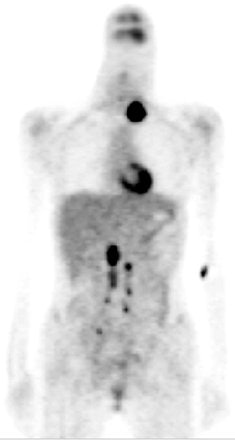

| A 25-year-old woman with poorly differentiated squamous cell carcinoma of the uterine cervix, FIGO stage 111b, underwent concurrent chemoradiation therapy. Three months later, a left neck mass was palpated. Abdominopelvic MRI and chest CT showed no definitely abnormal findings except an enlarged supraclavicular lymph node. |

| In a mix of salvage radiotherapy and palliation treatment, PET was performed and suggested nodal metastases at the left supraclavicular, the bilateral upper and lower para-aortic, and the bilateral pelvic regions. After the left supraclavicular and para-aortic nodal metastases were confirmed histopathologically, patient received palliation treatment. Reprinted by permission of the Society of Nuclear Medicine from Yen TC, See LC, Chang TC, et al, "Defining the Priority of Using 18F-FDG-PET for Recurrent Cervical Cancer" (J Nucl Med 2004; 45: 1632-1639, p. 1634 [Figure 1]). |